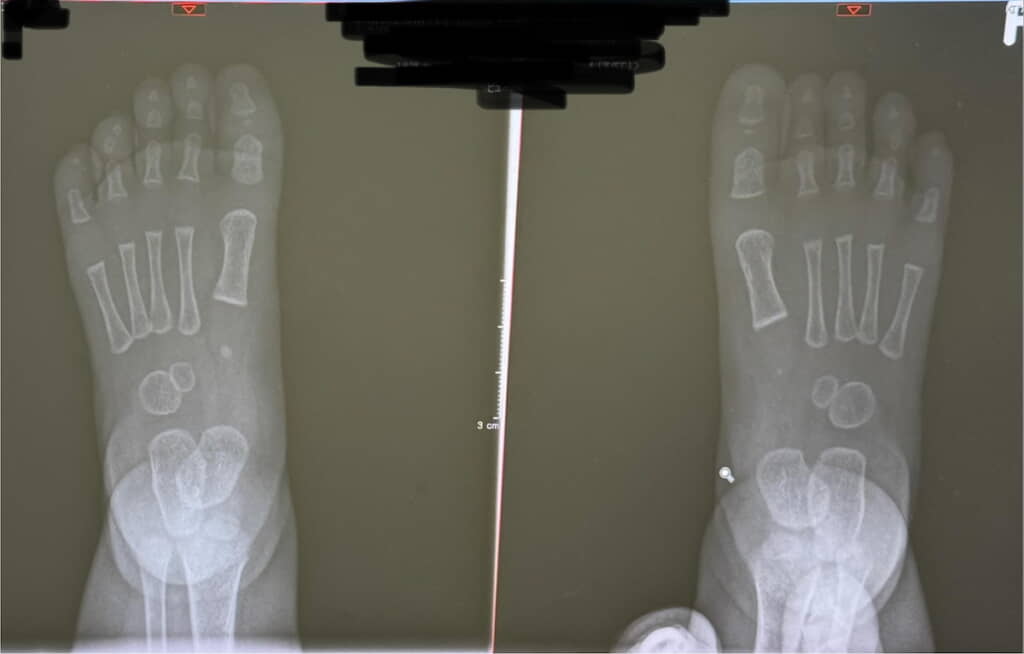

投稿者は、生後9カ月の女の子を育てるママ(@mi_kichi1211)さん。「エケチェン(赤ちゃん)の足のレントゲン」として紹介するのは、娘さんの足首から先を撮ったレントゲン写真です。

レントゲン写真では、赤ちゃんらしいむちむちとした足首周りと、発育途上の小ぶりな骨が確認できます。骨と骨の間が広いのは、子どもの足ではおよそ70%が軟骨で構成されているためです(参考:ムーンスター「子どもの足の構造」)。

ママさんは、「骨の感じといい、むちむち感が伝わる感じも含めてかわちい」と我が子の足にほれぼれする様子をつづっています。確かにとってもかわいいですね!